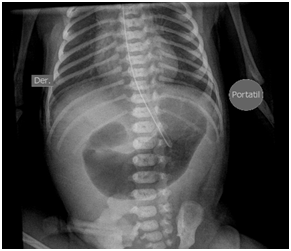

Newborn female was born at 37 weeks 5 days as a product of a second pregnancy, with prenatal diagnosis of duodenal atresia and esophageal stenosis (Figure 1). Due to a previous cesarean section and rupture of the membranes, an emergency caesarean section was performed. Birth weight was 2100 grams APGAR scores were 8–9 at…min. A thoracic-abdominal radiograph was performed, showing thorax without alterations and an image suggestive of duodenal atresia (Figure 2). An echocardiogram CIA 0.5, PCA: 0.2X0.3 showed mild dysplasia of aortic and pulmonary valves. Abdominal laparotomy at 24hours of life, revealed duodenal stenosis secondary to annular pancreas, intestinal malrotation and non-meconium plastic peritonitis without evidence of perforation. The defect was corrected by adhesiolysis, duodeno-duodenal anastomosis and incidental appendectomy.

Figure 2 Thoracic-abdominal radiography before corrective atresia surgery.